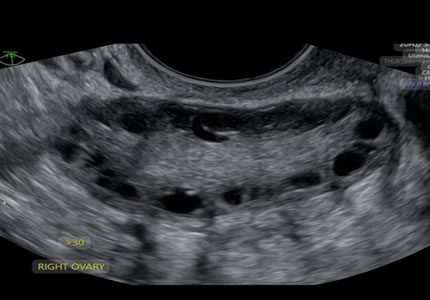

Comprehensive pelvic ultrasound evaluations for a wide range of non-pregnancy female health concerns, symptoms, or referrals.

Symptom-Based & Condition-Specific Scans